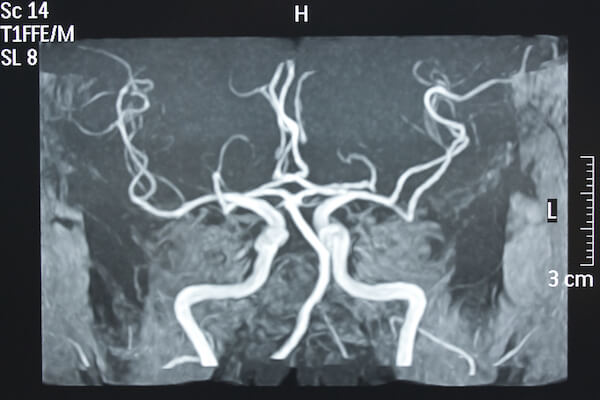

- embolizzazione di aneurismi cerebrali attraverso la tecnica del coiling o l’impianto di flow diverter

- stenting intracranico (sia per il trattamento delle stenosi cerebrali che per l’assistenza all’embolizzazione di aneurismi)